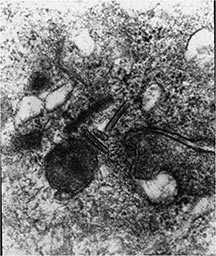

- Birbeck Granules: Electron Microscopy demonstrates granules that often take the form of a tennis raquet and form from complex invaginations of the cell membrane